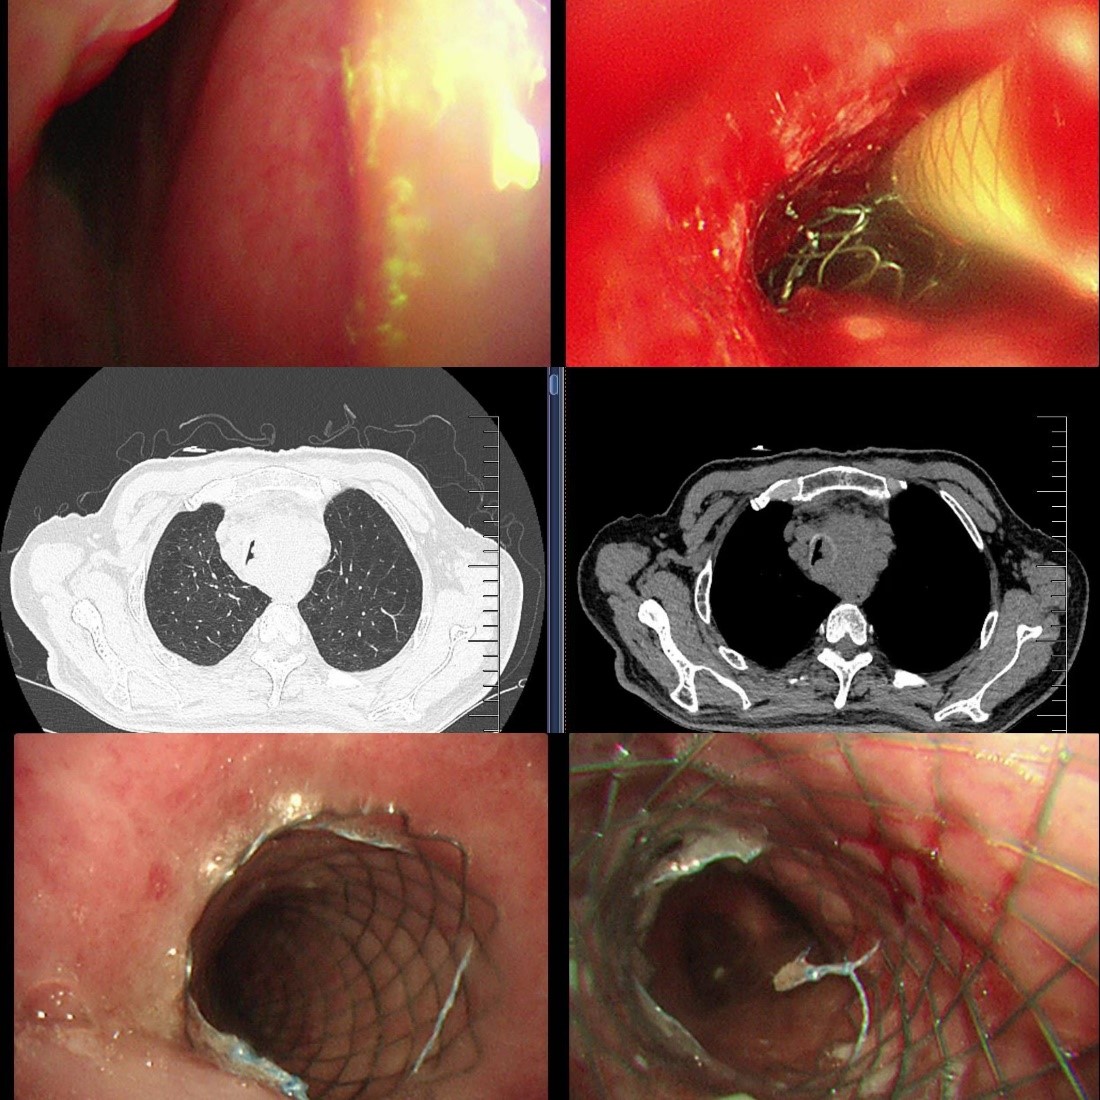

迅速排除手术禁忌,蒋军红主任团队为龚先生实施“支气管镜下主支气管支架置入术”。术中可见声门下4cm处气管呈混合性狭窄,狭窄长度约2cm,团队精准定位后,成功置入一枚16×40mm金属裸支架。术后2天复查气管镜,支架贴壁良好,仅少量肿瘤从网眼生长,经APC消融治疗。龚先生的胸闷、气喘明显缓解,顺利出院继续后续肿瘤治疗。

蒋军红主任团队冷静制定策略:使用APC(氩等离子凝固术)对新生物进行局部消融,减少阻塞,稀释肾上腺素、冰盐水止血,随后快速的在原有支架腔内最狭窄部位,精准叠加置入一枚12×30mm金属裸支架。操作过程顺利,术后支架通畅度显著提升,远端管腔无明显狭窄,同步留取灌洗液送检明确感染与肿瘤情况。